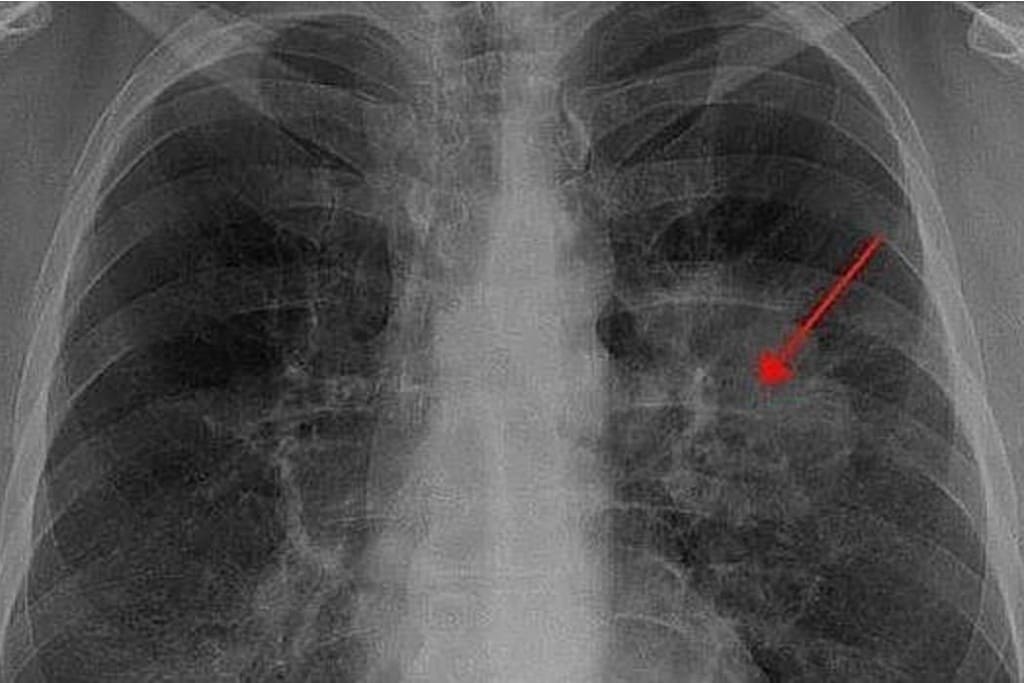

- Neumonitis por radiación (aguda): Es una reacción inflamatoria que ocurre entre el primer y tercer mes después de la radioterapia.

- Síntomas: Tos seca, disnea (dificultad para respirar), fiebre y dolor torácico.

- Fibrosis por radiación (crónica): Es el resultado del daño a largo plazo y aparece uno o dos años después.

- Síntomas: Dificultad para respirar progresiva, insuficiencia respiratoria e insuficiencia cardíaca.